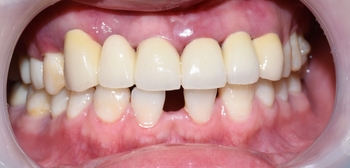

최종적으로 요렇게 완성이 되었구요 끼운 당일날 사진입니다.

사실 이렇게 이를 드러낼 일은 없죠

환자분이 관리를 잘 하신다면 치아사이의 검은 공간도 잇몸으로 메워져서 더 자연스럽게 될 것으로 생각합니다.

색상도 실제 입안에서는 훨씬 자연스럽구요

편안히 입술을 어느정도 벌리셨을때 이 정도 자연스러움이 나옵니다.

치아 색상도 모양도 좋아지고 고르게 되고 공간도 없어져서 환자분도 만족!

물론 건드리지 않은 아래쪽은 공간이 있지요..